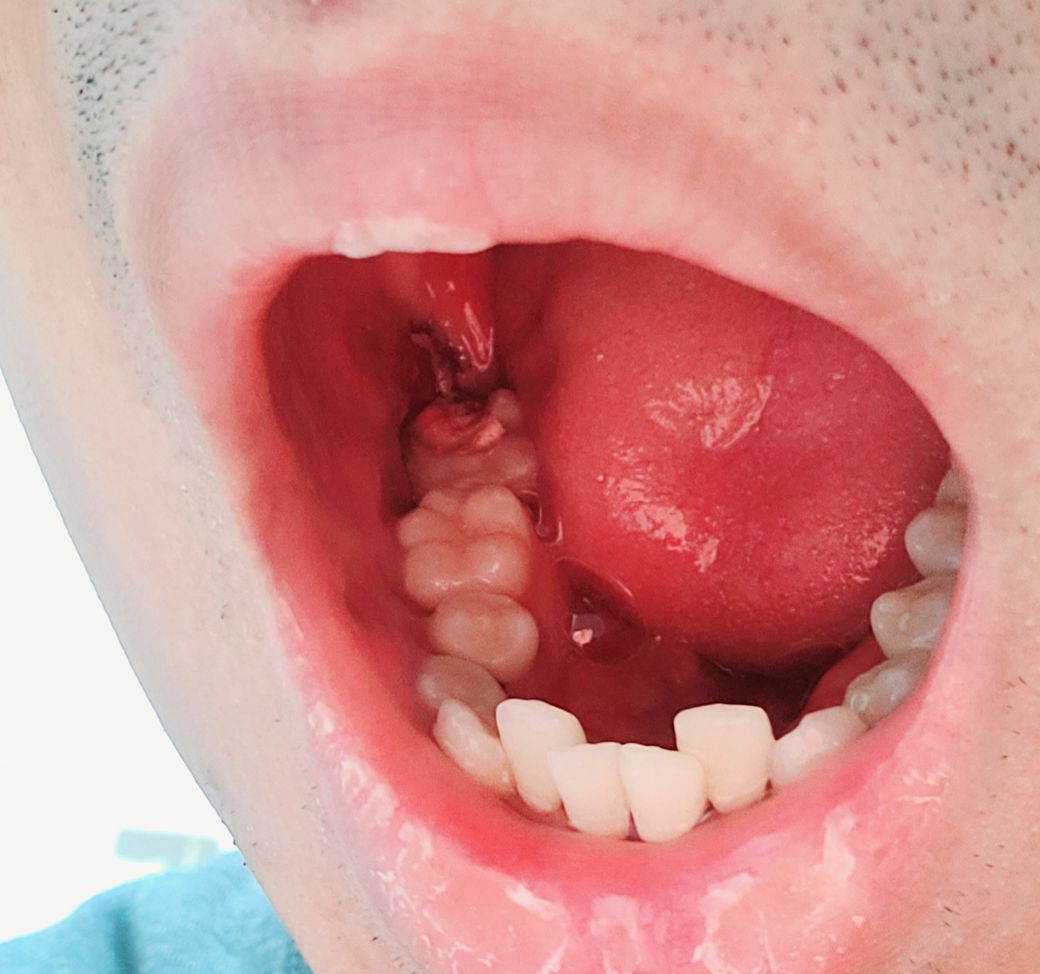

이거 드라이소켓은 아니겠죠???.

제가 사랑니발치한지 4일째인데 아침에 일어나면 통증조금있다가 없어지고 또 붓기 있다가 5분에서 10분쯤 지나면 가라앉던데 이거 드라이소켓은 아니겠죠? 약을 3일치 받았습니다 그리고 볼이 조금 씹혀질려고합니다.,.

드라이 소켓은 감염떄문에 발생하는 걸로 냄새가 많이 나고 통증이 극심합니다. 드라이 소켓은 아니신거 같습니다.

사진으로 보아 정상적으로 아물고 있는 것으로 보입니다. 지금 4일째 통증이 있다면 약국에서 파는 진통제 추가로 사서 드셔도 됩니다.

1. 일단 드라이소켓의 가능성은 크진 않아 보입니다

드라이소켓이 생기면 매우 극심한 통증이 생기고 냄새가 많이 나기 때문에 드라이소켓은 아닙니다.

사진으로 많은 드라이 소켓의 여부를 판단하기 힘들어 보입니다.

드라이 소켓이 있는 경우 극심한 통증과 악취가 나기 때문에 드라이 소켓인 경우에는 쉽게 구분할 수 있습니다 자세한 확인을 위해서 치과에서 진료를 받아 보세요